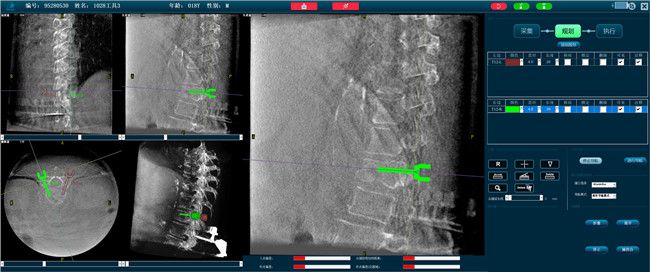

步驟二:手術實施

在病人體表切開一個長1-2cm的創口,沿骨科機器人的機械臂定位點方向將克氏針導向套筒,通過創口送至病灶椎體處,并沿套筒方向打入克氏針進行定位。沿導針插入工作套管,取出導針,完成球囊擴張后,通過骨水泥注入器準確地在骨折部位緩慢注入骨水泥,幫助其恢復椎體的形狀和強度。